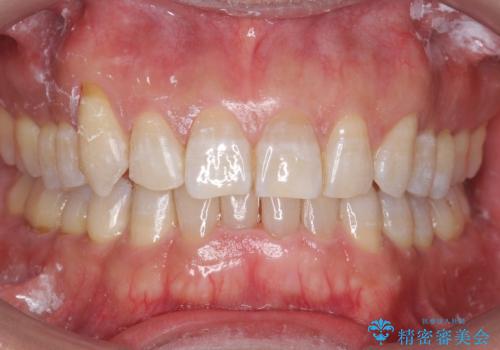

八重歯と下の歯のがたつき マウスピースで

- 右上の犬歯が目立つのが気になる、下の歯並びも治したいとのことで来院。

歯を抜かずに少し削って小さくして並べました。

並びも良くなり、患者様にも喜んでいただきました。

右上の犬歯の歯肉退縮自体は進行する可能性をお伝えしておりましたが、特に変化なく治療できました。

歯肉退縮につきましては、歯ぐきの移植を提案しましたが特に希望されませんでした。